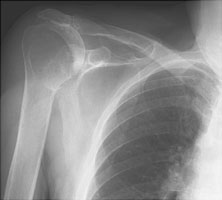

- Click on the image for a larger versionCAP chest radiograph. The usual appearance of an anterior shoulder dislocation on a frontal radiograph.